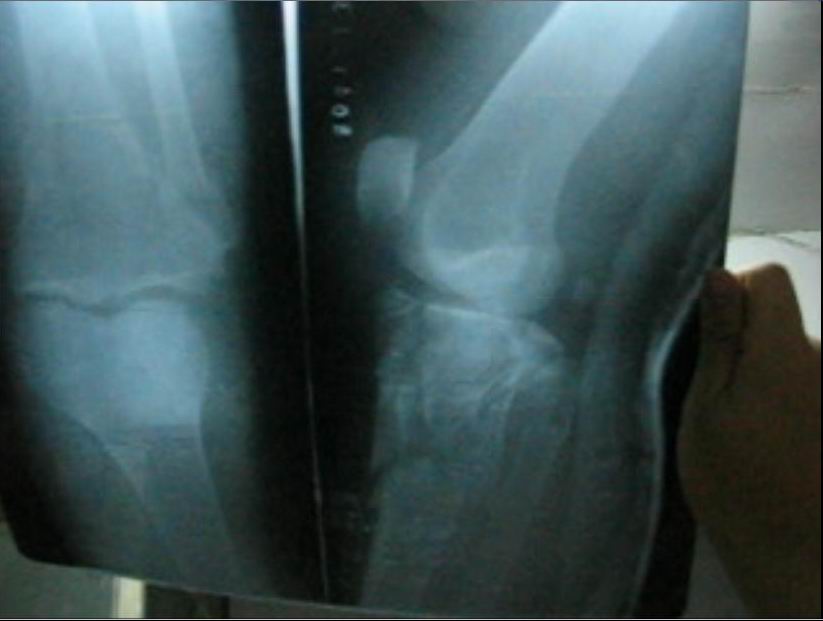

焦龙下来时不慎把左腿摔成粉碎性骨折。被抓后因不能行走,恶警就拽着焦龙的胳膊在地上拖着走,一直拖进车里,他们并没有把他送进医院,而是拉到了团结路派出所,下车时他们还是拽着胳膊在地上把焦龙拖进屋里,并开始对他非法审讯。恶警董某甚至用脚踢他受伤的腿。

而后他们把焦龙送到大庆医院拍片子,拍完后发现多处骨折。从医院他们用车把焦龙拉回派出所,没让他下车。说市里来人正在开会研究,后来出来一位领导模样的人对他说:我们放你走,在大庆有没有亲朋好友,把你接回去治伤。

这样焦龙被出租车司机送走。因为耽误及时救治,他的腿肿得象小水桶一样粗,脚肿得也很高。后来辗转来到外地,直到现在他的腿还没有恢复正常。

下面是焦龙的腿摔骨折后的照片。